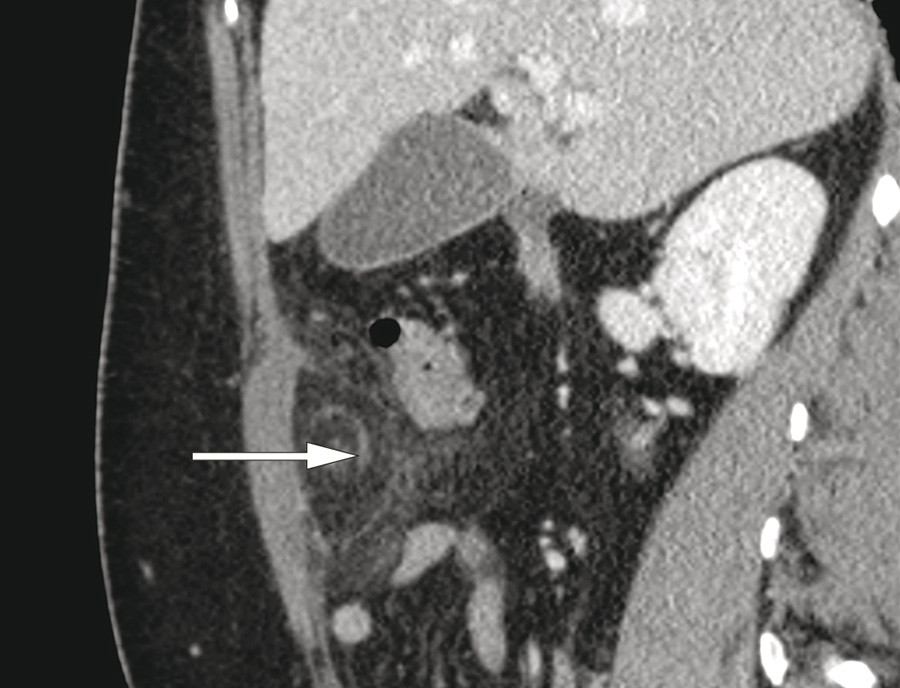

En kvinne i 40-årene ble innlagt med magesmerter, mest uttalt under høyre kostalbue. Smertene var konstante og hadde oppstått tre dager tidligere. Hun var ikke tidligere operert i buken. Ved klinisk undersøkelse var abdomen bløt med palpasjonsømhet i øvre høyre kvadrant. Bortsett fra forhøyet CRP på 80 mg/l (< 5) var alle blodprøver normale. Ultralydundersøkelse av lever, galleblære og pancreas ved innkomst viste upåfallende forhold. På grunn av vedværende sterke smerter ble pasienten undersøkt med CT abdomen samme dag. CT-undersøkelsen viste et avkapslet område av mesenterialt fettvev ventralt i øvre høyre kvadrant. I koronalplan (bilde til venstre) indikerer pilen det avkapslede området. I sagittalplan (bilde til høyre) så man tydelig en spiralformet forandring, som kunne representere roterte kar og mesenteriale strukturer (pil). Pasienten ble laparoskopert og det ble funnet en partiell torsjon av omentum majus. Det torkverte segment lå adherent mot bukveggen og inneholdt begynnende nekrotiske forandringer og ble fjernet.